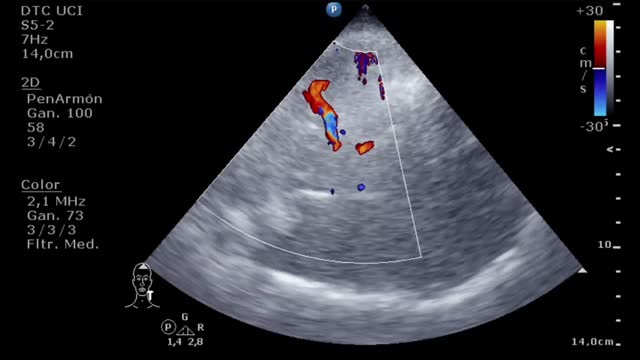

En la evaluación para el implante de una ECMO VV otro factor esencial es la función del ventrículo derecho (VD). Muchos pacientes con síndrome de distrés respiratorio agudo grave presentan hipertensión pulmonar y disfunción del VD en relación con la hipoxia, la hipercapnia, el aumento de la presión de las vías aéreas y la ventilación mecánica. La ECMO VV, al corregir la hipoxia y la hipercapnia, disminuye la poscarga y puede mejorar la función del VD de manera que se corrija la inestabilidad hemodinámica. En caso de presentar una disfunción ventricular derecha significativa será importante realizar un seguimiento ecocardiográfico y, si se perpetúa la situación de shock y no mejoran los parámetros ecocardiográficos a pesar de la ECMO VV, habría que plantear un cambio de estrategia a un VA o veno-arteria-vena. Para la evaluación de la disfunción del VD valoraremos: desplazamiento sistólico del plano del anillo tricuspídeo<16mm, onda S’<10cm/s, fracción de acortamiento<35%, relación área telediastólica VD/VI>0,6 significativa y >1 grave o aplanamiento/abombamiento (en forma de «D») del septo interventricular tanto en sístole como en diástole (suplementario 1). Esta interdependencia se puede cuantificar a través del índice de excentricidad ventricular, que es el cociente entre el diámetro septo-cara inferior y cara anterior-cara inferior en sístole y diástole, siendo su valor normal=118.